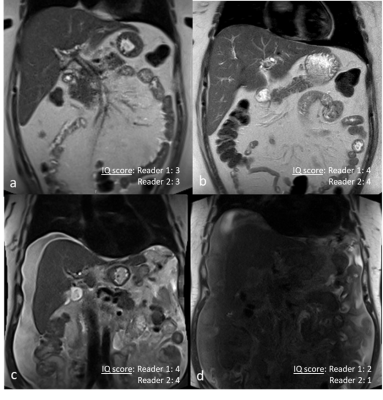

Comparison of 0.55T and 1.5T in 2 patients. Coronal SS T2w TSE in a patient Primary Sclerosing Cholangitis at 0.55T(a) and 1.5T(b). Because of low SNR on 0.55T, lower IQ score were assigned by both readers to (a) compared to (b). Coronal SS T2w TSE in another patient with ascites at 0.55T(c) and 1.5T (d). There is central signal loss at 1.5T(d) resulting in a lower rating on 1.5T(d) compared to 0.55T(c)